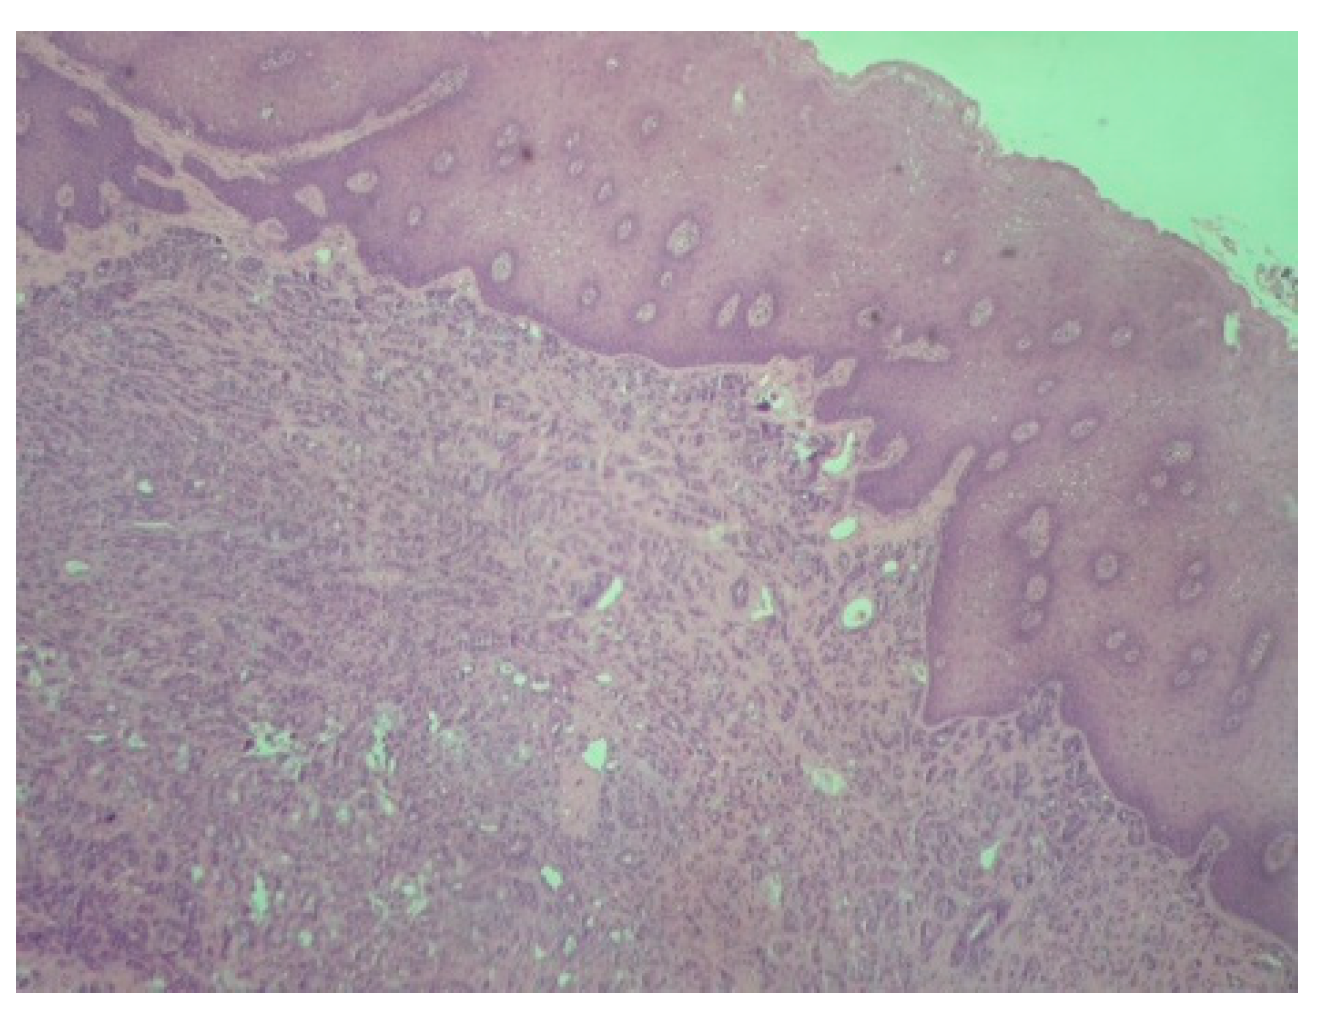

2. Case Presentation